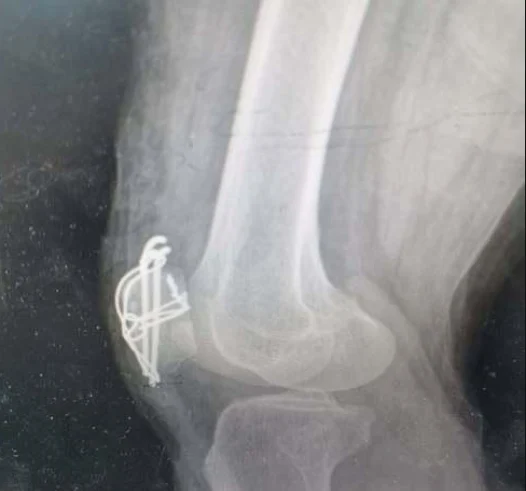

手术治疗适用于移位明显或粉碎性骨折。常见的手术方式包括张力带固定、髌骨切开复位内固定等。手术旨在恢复骨折断端解剖对位,确保髌骨正常功能和形态。手术后,患者应遵循医生建议进行康复训练,以最大限度恢复正常功能(《Lancet》, 2018)。